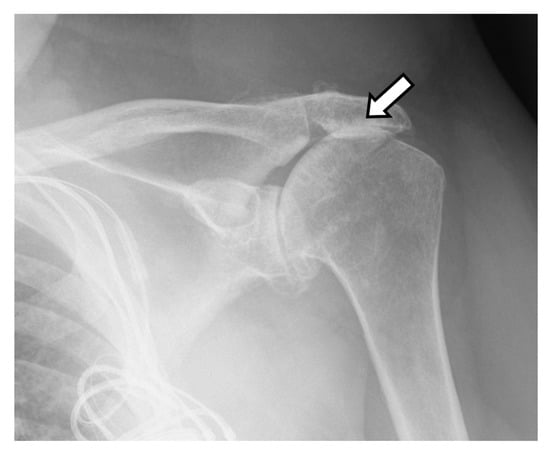

4.3. Unique Complications

- Lau, S.C.; Large, R. Acromial fracture after reverse total shoulder arthroplasty: A systematic review. Shoulder Elb. 2019, 12, 375–389. [Google Scholar] [CrossRef] [PubMed]

- Nyffeler, R.W.; Altioklar, B.; Bissig, P. Causes of acromion and scapular spine fractures following reverse shoulder arthroplasty: A retrospective analysis and literature review. Int. Orthop. 2020, 44, 2673–2681. [Google Scholar] [CrossRef]